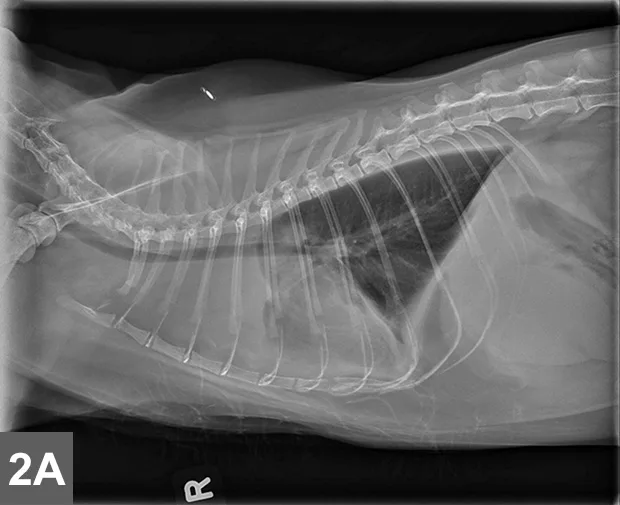

FIGURE 1

EATL type II (small cell) is the most common intestinal LSA in cats (A) and requires immunohistochemical labeling for proper phenotypic characterization and often PARR testing to differentiate from IBD. (B) EATL type I (large cell) occurs less commonly in the small intestine of cats, and neoplastic cells are often large granular lymphocytes. (C) Diffuse large B-cell lymphomas (DLBCL) occur most commonly in the stomach of cats or may present as part of multicentric disease. Although LSA diagnosis is usually made with routine microscopic examination, immunohistochemistry is required to accurately differentiate EATL type I from DLBCL (magnification 40×). Image and description courtesy of Matti Kiupel, Dr. vet. med. Habil, MS, PhD, DACVP, Michigan State University.

• Enteropathy-associated T-cell LSA (EATL) type I (high-grade or large cell/lymphoblastic GI LSA)1,6-7

• Typically involves more intermediate to large cells that display transmural invasion and often form masses (Figure 1B).

• Intermediate to large B-cell LSAs, including diffuse large B-cell  lymphoma (DLBCL), also occur with slightly less frequency (Figure 1C).

• Large granular LSA (LGL)—an aggressive subtype of EATL type I—is comprised of either cytotoxic T-cells or NK cells and characterized by multiple masses within the GI tract and other organ systems.8

• EATL type II

• The more common presentation of GI LSA characterized by diffuse superficial (mucosal/lamina propria) infiltration of small T-lymphocytes that often display epitheliotropism (Figure 1A).1,5-7

• Referred to as low-grade, lymphocytic, small cell, or indolent GI LSA, and associated with a slowly progressive disease course.1,5-7